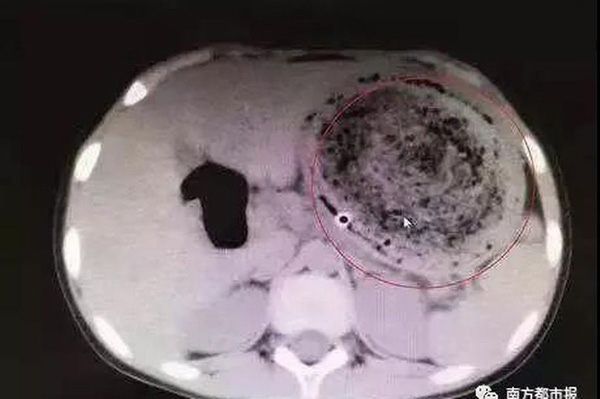

Tại đây, Feifei được rửa dạ dày nhưng bác sĩ không tìm thấy dư lượng thực phẩm nào mà là một búi tóc rối rất lớn cuộn với cặn thức ăn. Tuy nhiên, không thể loại bỏ được nó thông qua nội soi vì đã có dấu hiệu vôi hóa. Bác sĩ đã phải thực hiện phẫu thuật mổ dạ dày để có thể lấy búi tóc nặng đến gần 1,5kg ra khỏi bụng cô bé.

“Búi tóc ‘khổng lồ’ này đã có trong dạ dày bé gái nhiều năm. Thói quen ăn tóc là một triệu chứng điển hình của Pica - một chứng rối loạn ăn uống khiến người bệnh có xu hướng ăn các vật không có dinh dưỡng”, bác sĩ giải thích và nhắc nhở các bậc cha mẹ hãy để mắt đến những thứ mà con cái họ ăn.